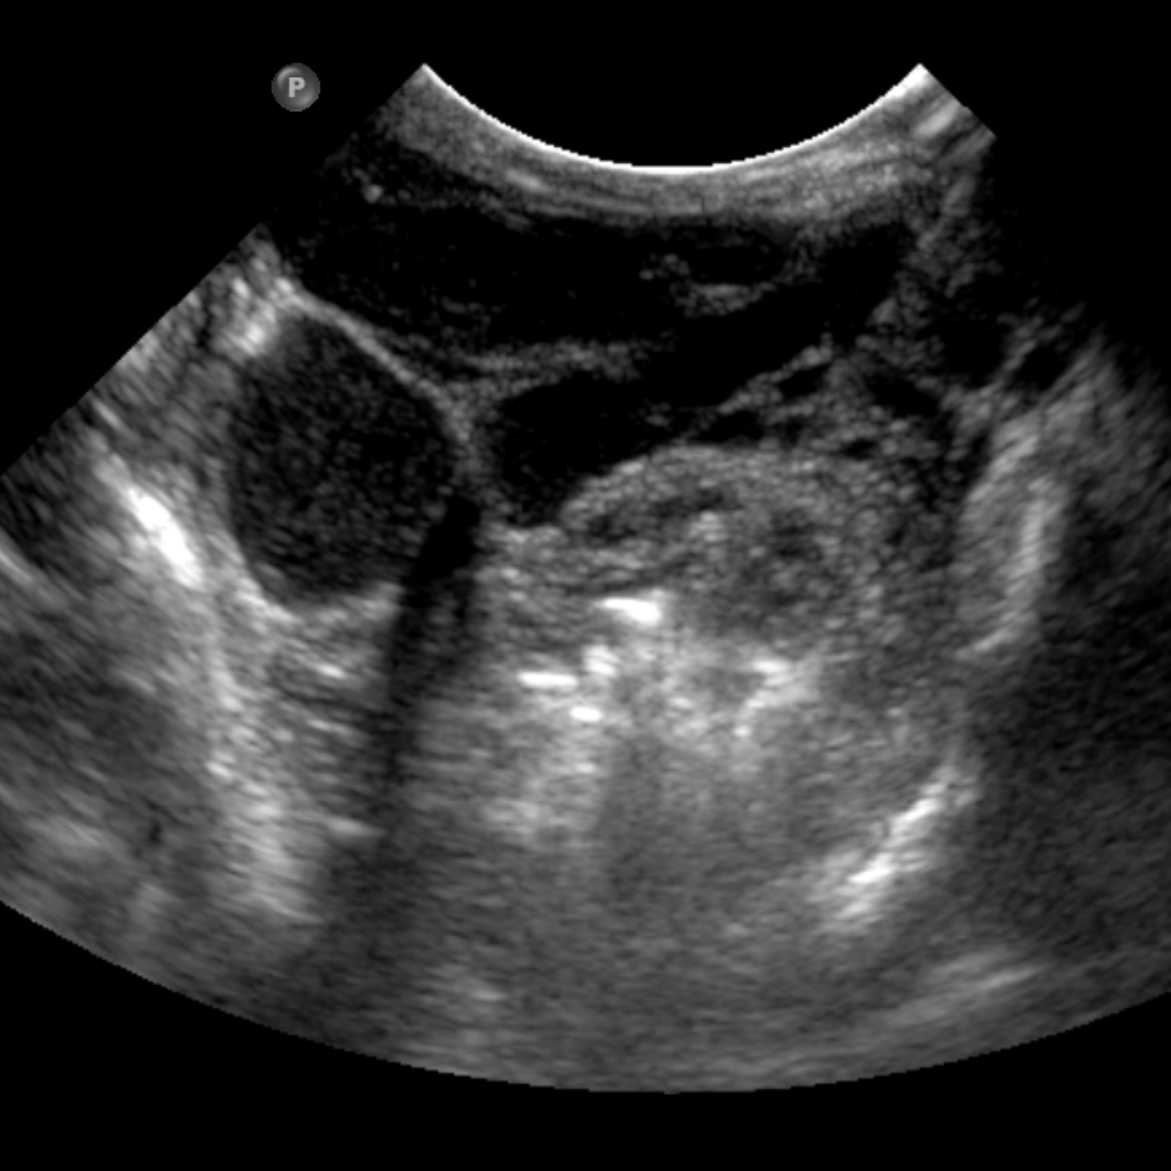

When treating small LM cysts, US guided injection can be performed slowly and in a controlled way watching the agent in real time spread through a geographic area of the lesion. Often multiple needle punctures will be needed to fill a lesion. We use this technique for injection of Doxy and Bleo foams.

MRI of small LM cysts (top), US of needle injecting individual cysts (left), photo of US guided technique for small cyst puncture (right).